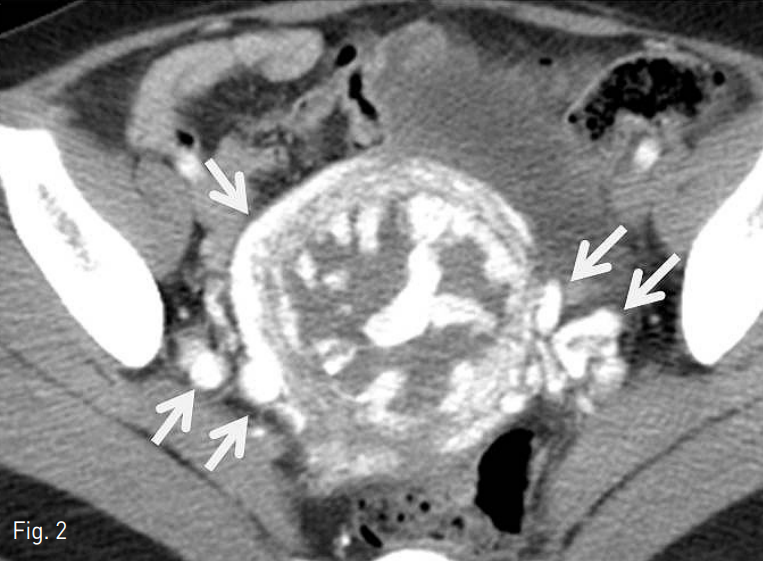

5Fr pigtail 카테터 (Cook, Bloomington, IN, USA)를 이용한 골반동맥 조영술상에서 자궁 동정맥기형이 확인되었다 (Fig. 3). 5Fr Cobra 카테터(Cook, Bloomington, IN, USA)를 이용하여 양측 자궁동맥을 선택한 후 5Fr 카테터 내부로 2.2Fr 미세도관 (Progreat; Terumo, Tokyo, Japan)을 삽입하여 양측 자궁동맥에 대하여 젤폼 (Cutanplast; Mascia Brunelli, Milano, Italy)으로 색전술을 시행하였다. 그러나 혈류가 지속적으로 남아 있어서 유입 혈류를 줄여주기 위하여 양측 자궁동맥의 근위부에 미세코일 (5mm x 5cm 4EA, 4mm x 4cm 2EA, 3mm x 2cm 2EA, Tornado,Cook, Bloomington, IN, USA)을 이용하여 색전술을 추가로 시행하였다. 또한 좌측 폐쇄동맥 (obturator artery)과 좌측 방광동맥 (vesical

Fig. 3

Initial pelvic angiography shows hypertrophied abnormal vascular structures in uterine shadow, supplied by both uterine arteries and other mul ti ple extrauterine feeders.